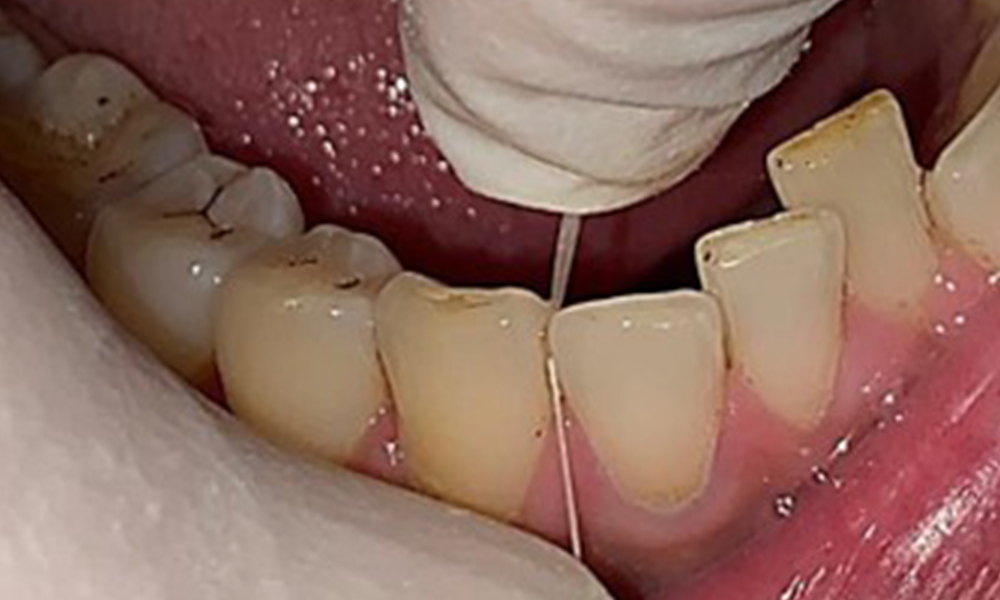

Résultats dentaires

Le patient a une dentition complète avec un total de 28 dents. Il y avait des érosions et des attritions notables. (Fig. 4, Fig. 5). En raison du bruxisme, le patient a porté pendant de nombreuses années une attelle avec une gouttière ajustée la nuit. Les érosions ont été causées par une consommation prolongée de boissons isotoniques. Aucune perte d'os parodontal ou carie active n'a été observée.

Vue rapprochée des dents

Fig. 5: Vue rapprochée des dents 45 à 47. Les flèches vertes montrent l'attrition dentaire et les érosions des cuspides buccales avec perte partielle d'émail., © Dr R. Krapf